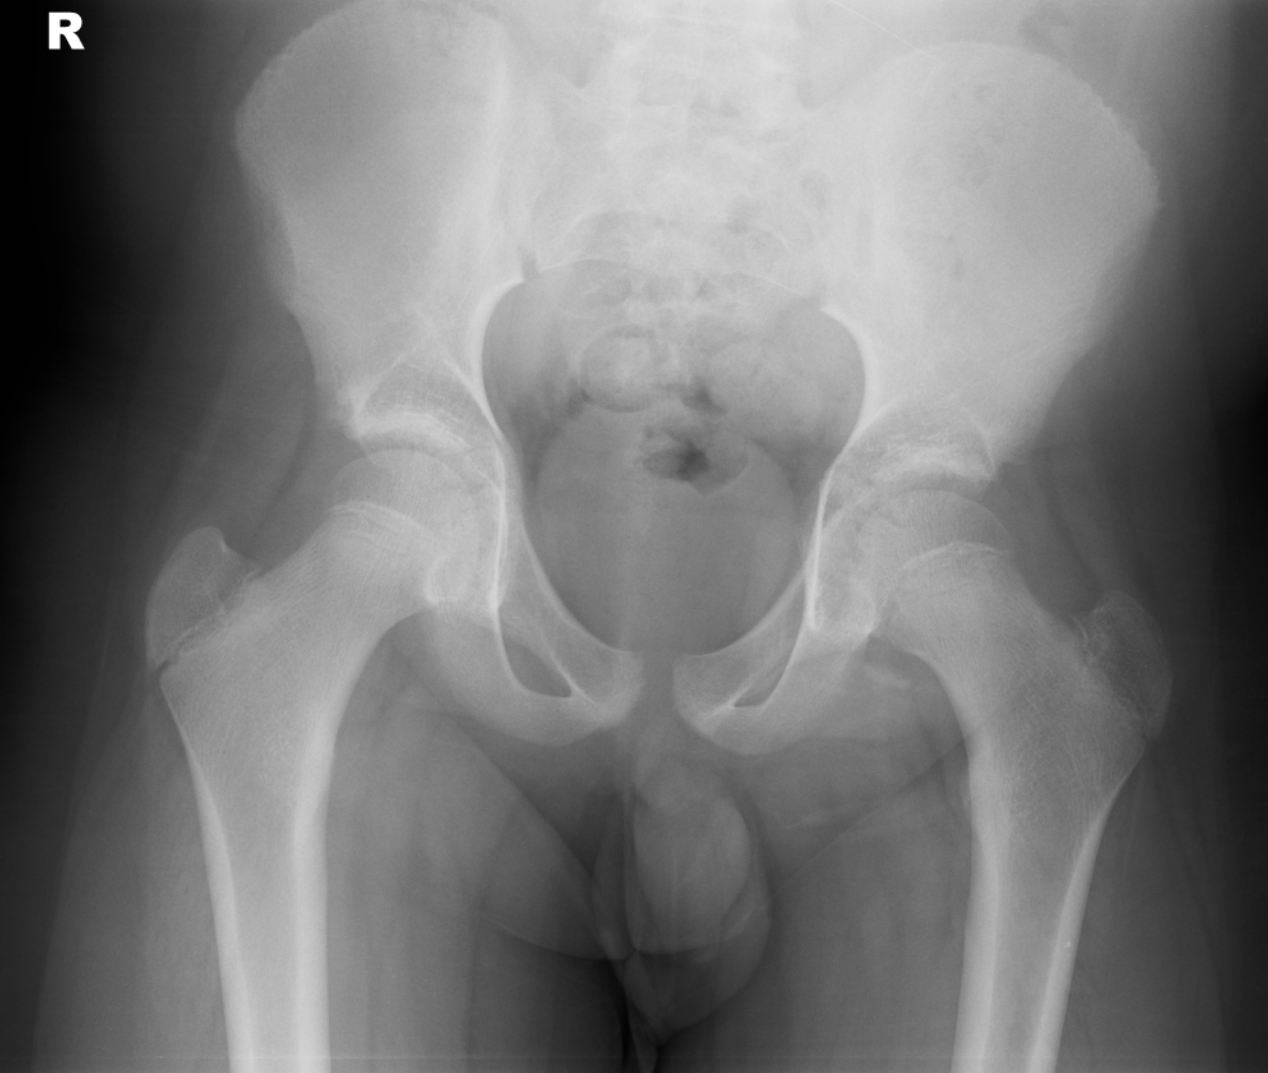

CASE 2

HISTORY

Young patient. Bilateral hip pain. No direct trauma.

QUESTION

Concentrate on the hip joints. On this AP radiograph - are the hips normal?

RADIOGRAPHS

ANSWER